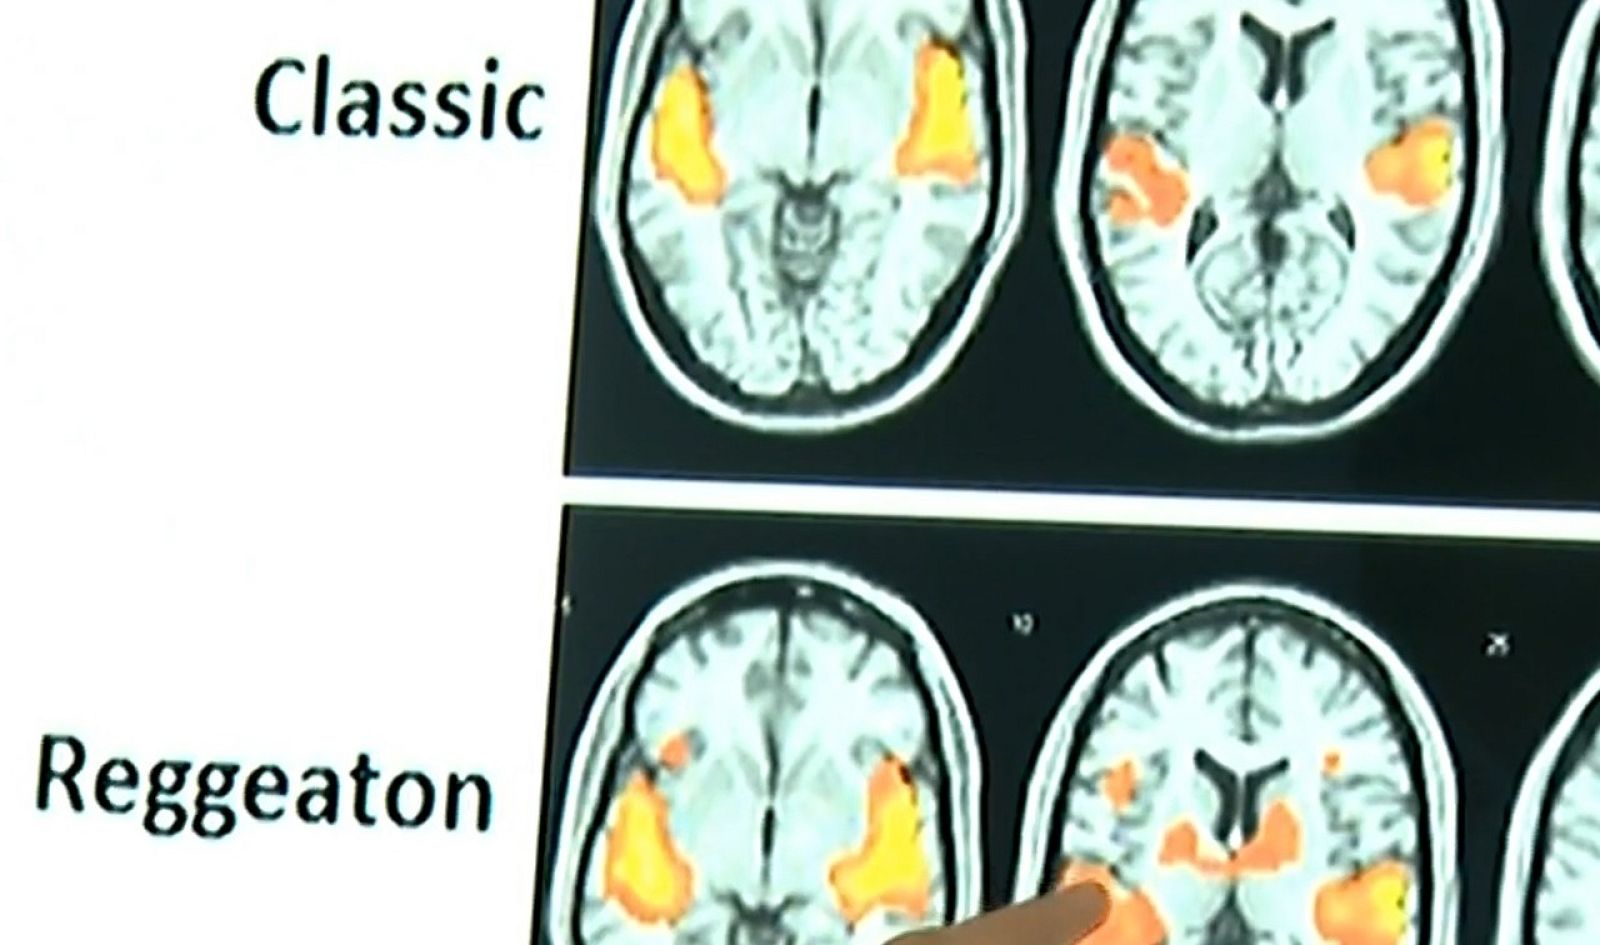

El reguetón activa el cerebro "muchísimo más que los demás estilos" musicales

Un equipo de investigadores canarios ha estudiado cómo reacciona el cerebro ante distintos géneros musicales, entre ellos, el reguetón, capaz...